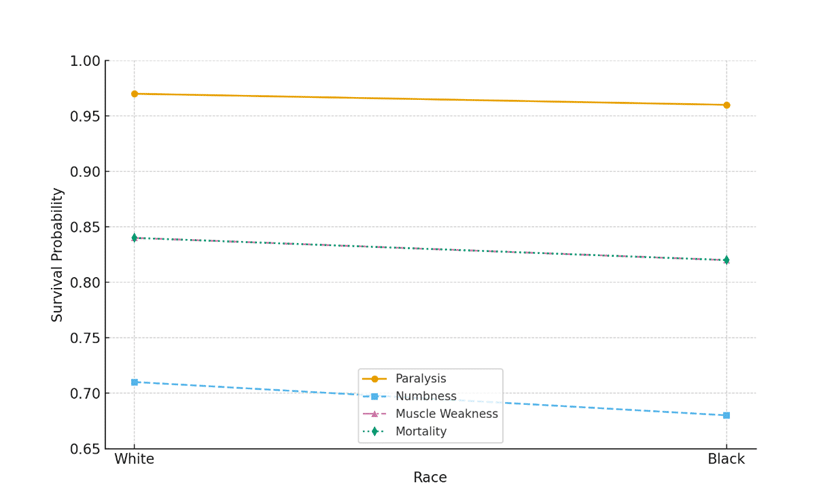

Racial Differences in Guillain-Barré Syndrome Outcomes: One-Year Retrospective Analysis

Introduction: Guillain-Barré syndrome (GBS) is a sudden-onset autoimmune disease of the nerves, which leads to paralysis and muscle weakness, impaired...Read More